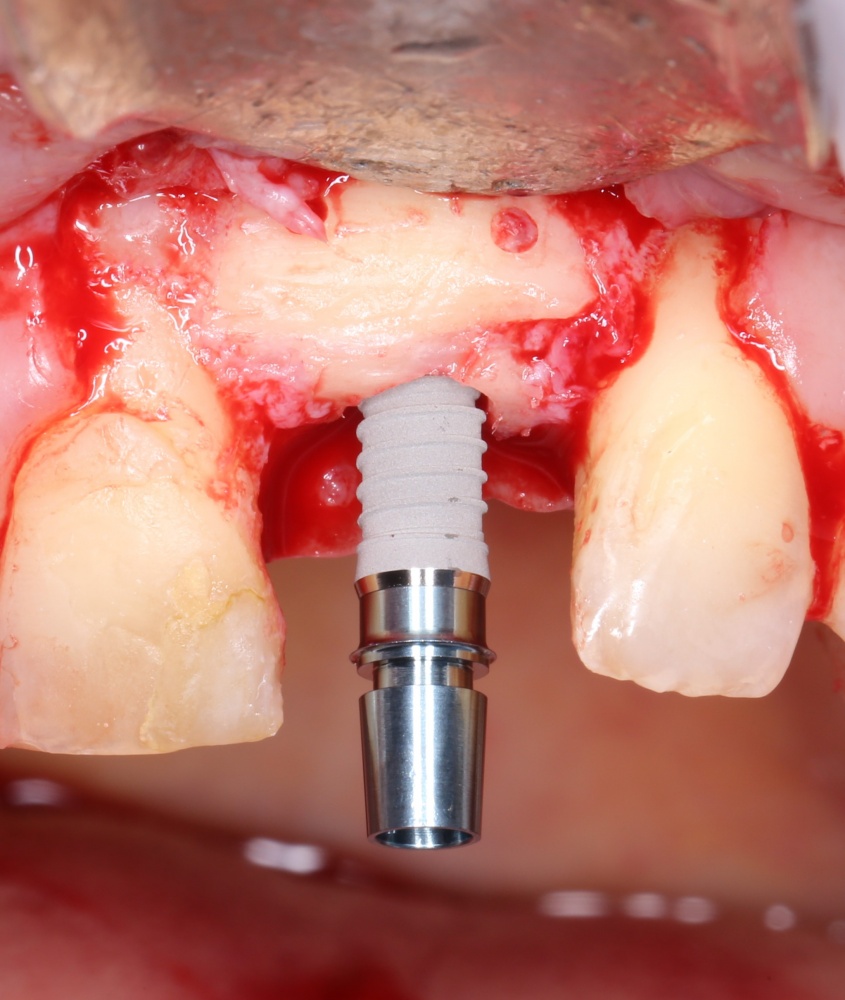

Подготовка лунок для имплантатов

Прежде, чем приступить к аугментации (пластике) лунок зубов, мы подготовили лунки для имплантатов. В таких клинических случаях нет необходимости в использовании шаблона. Вместо этого, мы применяем общепринятые правила позиционирования и соблюдаем рекомендации производителя по хирургическому протоколу:

В процессе ирригации лунки промываются, что позволило нам еще раз подтвердить ранее сделанные выводы. С помощью аналогов имплантатов, входящих в хирургический набор Xive, мы проверили возможность стабилизации имплантатов в будущих лунках. Исходя из правил подбора и позиционирования имплантатов (я очень рекомендую почитать об этом здесь>>) мы остановились на Xive S диаметром 3,4 мм и длиной 13 мм.

Подготовка двух лунок для имплантатов занимает около 10 минут.

Трансплантация десны, аугментация лунки

Для определения размеров будущего мягкотканного аутотрансплантата мы использовали пародонтологический зонд. С помощью него мы выбрали донорскую зону (бугор верхней челюсти или небная сторона альвеолярного отростка верхней челюсти в области моляров), с помощью скальпеля получили необходимый по размеру аутотрансплантат (мягкотканный лоскут для пересадки).

Затем, мы подготовили ксенографт Bio-Oss Collagen. Обычно на 2 зуба (центральных резца) с избытком хватает 100-миллиграмовой упаковки. Имеющийся в ней параллелепипед мы поделили на 2 усеченные пирамиды с основанием в 2/3 ширины изначального блока.

Если вы когда-нибудь видели подобные операции, то наверняка обращали внимание на порядок действий — сначала устанавливаются имплантаты, затем укладывается графт и только потом фиксируется мягкотканный аутотрансплантат. Для удобства в этом и похожих клинических ситуациях мы поменяли порядок действий:

Сначала мы провели и зафиксировали деэпителизированный соединительнотканный аутотрансплантат (ССТ). Для этого мы сформировали тоннель и использовали ортодонтическую проволоку в качестве проводника. Подробнее об этой методике можно почитать здесь>>.

Затем уложили ксенографт. Особенностями Bio-Oss Collagen являются удобство адаптации, устойчивость к вымыванию и выдавливанию, поэтому мы просто уложили полученные ранее пирамидки вестибулярно относительно будущего имплантата, после чего прижали их с помощью уже упоминавшихся аналогов имплантата, входящих в хирургический набор имплантационной системы Xive (кстати, при работе с другими имплантационными системами для паковки графта в лунке можно использовать круглые остеотомы для синуслифтинга).

В совокупности, аугментация лунок перед установкой имплантатов занимает около 20 минут — и это самый долгий из всех хирургических этапов лечения.

Установка имплантатов